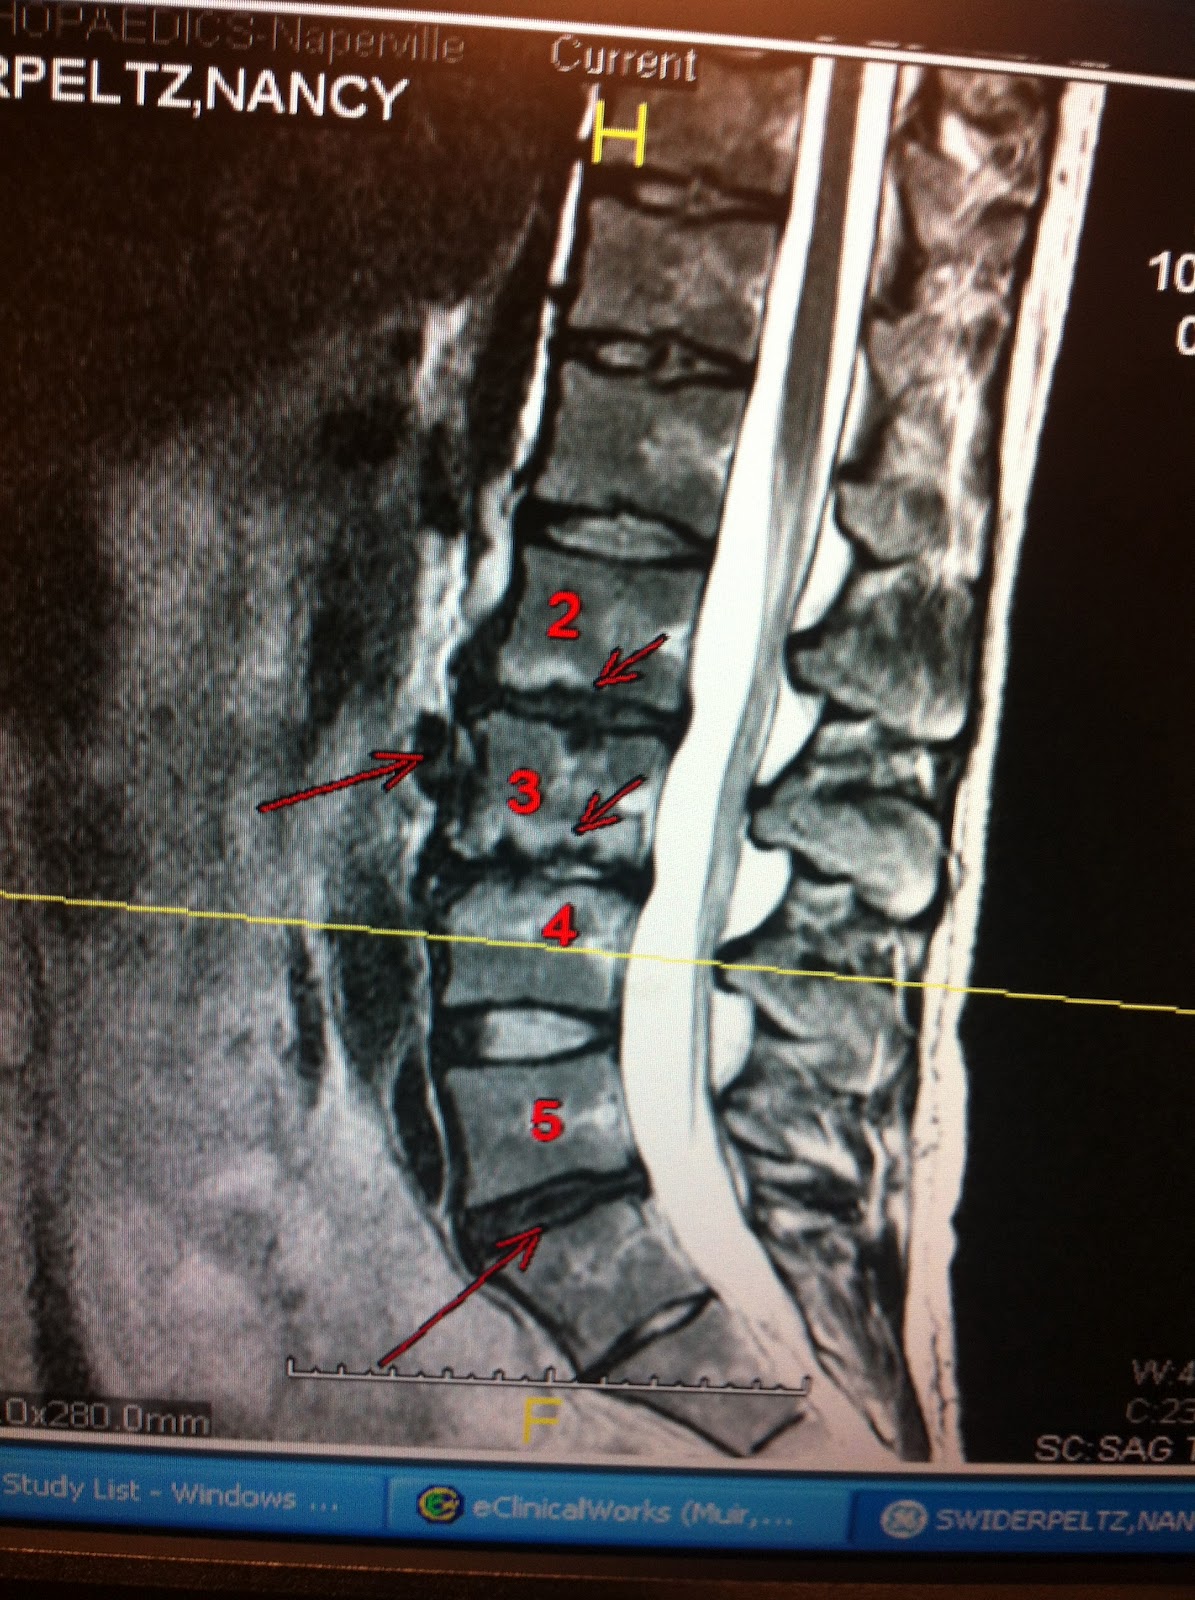

As we count down to our Fall World Cup Qualifier, November 2-4th...our bodies have started resting and mentally we are preparing for the racing season that is just around the corner. I'm pumped to finally put all my hard work from this past summer/fall to the test, but at the same time, there is definitely a little nervousness that stems from the unknown of how I will race. But it's the good nervousness! For myself, I've had a rocky road since the Vancouver Olympics, hitting road blocks each fall with injuries, so I've not had a normal competition season since 2009/2010. Next weekend will be a great test to see how my coach, my therapy team and I, have overcome these obstacles.